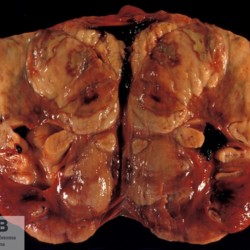

Etiquetes: N-173/96 de 2 Pàgina següent 6 total Canine Specie: Canine Organ: Kidney Lesion: Lymphoma Lesion modifier: - Disease: - Files/Expedient: N-173/96 Not viewed Canine Specie: Canine Organ: Kidney Lesion: Lymphoma Lesion modifier: - Disease: - Files/Expedient: N-173/96 Not viewed Canine Specie: Canine Organ: Kidney Lesion: Lymphoma Lesion modifier: - Disease: - Files/Expedient: N-173/96 Not viewed Canine Specie: Canine Organ: Kidney Lesion: Lymphoma Lesion modifier: - Disease: - Files/Expedient: N-173/96 Not viewed Canine Specie: Canine Organ: Heart Lesion: - Lesion modifier: - Disease: Dirofilariasis Files/Expedient: N-173/96 Not viewed de 2 Pàgina següent Títol Select...Avian (Exotic) (110)Avian (Poultry) (76)Bovine (317)Canine (935)Caprine (47)Equine (257)Feline (326)Ferret (19)General (127)Marine mammal (22)Non-human primate (20)Ovine (328)Porcine (379)Rabbit (61)Reptile (38)Rodent (28)Wildlife (91) Format Select...- (60)Abomasum (37)Adrenal gland (10)Blood (7)Blood vessel (50)Body as a whole (19)Bone (57)Bone marrow (21)Brain (93)Cloaca (1)Diaphragm (2)Ear (5)Esophagus (39)Eye (16)Fetus (12)Gallbladder (23)Gizzard (2)Heart (265)Intestine (356)Joint (32)Kidney (443)Larynx (5)Liver (326)Lung (264)Lymph node (91)Mammary gland (10)Mediastinum (1)Muscle (22)Nasal cavity (22)Nerve (7)Omasum (5)Oral cavity (63)Ovary (14)Oviduct (8)Pancreas (7)Parathyroid (5)Penis (10)Peritoneum (65)Pharynx (9)Pituitary gland (6)Placenta (7)Prostate (8)Proventriculus (3)Reticulum (1)Rumen (28)Sinus (7)Skin (181)Spinal cord (15)Spleen (105)Stomach (125)Teeth (1)Testicle (11)Thoracic cavity (31)Thymus (13)Thyroid gland (5)Tongue (32)Tonsils (11)Trachea (11)Urethra (5)Urinay bladder (61)Uterus (27)Vagina (1)Vulva (1)Yolk sac (1) Cobertura Select...- (152)Abomasitis (26)Abscess (27)Acidosis (1)Adenocarcinoma (20)Adenoma (9)Aerosacculitis (6)Agenesis (1)Agnathia (1)Alopecia (7)Amyloidosis (12)Aneurysm (6)Angiectasis (1)Anthracosis (1)Arteritis (11)Arthritis (15)Arthrogryposis (6)Artifact (4)Ascites (13)Atelectasis (8)Atherosclerosis (5)Atresia (1)Atrial septal defect (2)Atrophy (10)Autolysis (7)Bronchitis (6)Bronchopneumonia (26)Cachexia (2)Carcinoma (103)Cardiomyopathy (19)Cellulitis (2)Chemodectoma (4)Cholangiohepatitis (4)Cholangitis (19)Cholecystitis (4)Cholestasis (5)Chondrodysplasia (2)Chondrosarcoma (2)Chronic passive congestion (13)Chylothorax (2)Cirrhosis (6)Coelomitis (3)Coenurus cerebralis (4)Colitis (40)Congestion (17)Conjunctivitis (5)Coronitis (3)Cryptorchidism (3)Cyst (25)Cystitis (24)Dermatitis (69)Diaphragmatic hernia (4)Dilation (28)Discospondylitis (1)Disseminated intravascular coagulation (7)Dyschondroplasia (1)Dysplasia (29)Ectopia cordis (1)Ectopic ureter (1)Edema (55)Emphysema (5)Encephalitis (5)Endocardiosis (14)Endocarditis (26)Endometritis (5)Enteritis (118)Enterolith (6)Epulis (3)Esophagitis (14)Fasciitis (1)Fibrosis (7)Fibrous osteodystrophy (8)Fistula (1)Folliculitis (3)Fracture (2)Gastritis (34)Gingivitis (5)Glioma (8)Glomerulonephritis (21)Glossitis (25)Glycogenosis (1)Gout (8)Granuloma (2)Granulosa cell tumor (4)Hemangioma (9)Hemangiosarcoma (46)Hematoma (8)Hemoglobinuria (2)Hemopericardium (12)Hemoperitoneum (2)Hemorrhage (100)Hemosiderosis (7)Hemothorax (2)Hepatitis (78)Hernia (11)Histiocytosis (3)Hydatid cyst (11)Hydrocephalus (9)Hydrometra (1)Hydronephrosis (22)Hydropericardium (6)Hydrothorax (3)Hydroureter (5)Hyperkeratosis (8)Hyperostosis (4)Hyperplasia (37)Hypertrophy (9)Hypopigmentation (1)Hypoplasia (7)Hypopyon (1)Impaction (6)Infarction (63)Insulinoma (6)Intussusception (5)Jaundice (17)Laminitis (2)Laryngitis (2)Leiomyoma (5)Leukemia (13)Lipidosis (36)Lipoma (7)Lymphadenitis (45)Lymphadenopathy (7)Lymphangiectasia (6)Lymphangitis (5)Lymphoma (221)Malacia (11)Malignant melanoma (15)Mast cell tumor (11)Mastitis (8)Megaesophagus (2)Melanosis (3)Melena (4)Meningioma (6)Meningitis (6)Meningocele (2)Meningoencephalitis (5)Mesothelioma (5)Methemoglobinemia (2)Mineralization (10)Mucocele (5)Mucometra (1)Multilobular bone tumor (1)Mummification (3)Myelofibrosis (1)Myocarditis (4)Myositis (5)Necrosis (81)Nephritis (113)Nephroblastoma (6)Nephrosclerosis (1)Nephrosis (14)Neuritis (1)Obstruction (13)Omasitis (4)Omphalitis (1)Omphalophlebitis (7)Orchitis (4)Osteoarthrosis (5)Osteomyelitis (9)Otitis (2)Palatoschisis (3)Pancreatitis (3)Panniculitis (3)Papilloma (7)Parakeratosis (14)Patent ductus arteriosus (6)Peliosis hepatis (1)Perforation (17)Pericarditis (35)Peritonitis (39)Persistent right aortic arch (1)Pharyngitis (2)Pheochromocytoma (2)Phlebitis (2)Placentitis (6)Pleuritis (21)Pleuropneumonia (24)Pneumonia (109)Pneumothorax (3)Polycystosis (14)Polyp (5)Polyserositis (6)Posthitis (1)Proctitis (4)Prolapse (3)Prostatitis (3)Proventriculitis (1)Pyelonephritis (24)Pyometra (6)Pyothorax (4)Rhinitis (11)Rumenitis (6)Rupture (24)Salpingitis (3)Sarcoma (57)Sclerosis (1)Scoliosis (2)Seminoma (2)Sequestrum (2)Serous atrophy (14)Sinusitis (7)Splenitis (14)Splenomegaly (9)Spondylitis (6)Spondylosis (1)Stenosis (9)Stomatitis (32)Tenosynovitis (2)Teratoma (3)Thricobezoar (2)Thrombosis (16)Tonsilitis (4)Torsion (13)Tracheitis (4)Tympany (7)Typhlitis (8)Typhlocolitis (4)Ulcer (43)Urethritis (1)Urolithiasis (36)Uroperitoneum (1)Uveitis (1)Vasculitis (15)Ventricular septal defect (3)Volvulus (11) Matèria Select... - (14)- (1653)- (152)Abomasitis - Catarrhal (2)Abomasitis - Catarrhal-hemorrhagic (1)Abomasitis - Chronic (1)Abomasitis - Fibrinous-necrotizing (2)Abomasitis - Hyperplasic (5)Abomasitis - Hyperplasic - Chronic (1)Abomasitis - Necrotic (1)Abomasitis - Necrotizing (2)Abomasitis - Ulcerative (5)Adenocarcinoma (9)Aerosacculitis - Granulomatous (1)Amyloidosis - Chronic (1)Arteritis - Necrotic (2)Arteritis - Necrotizing (1)Arthritis - Chronic (4)Arthritis - Fibrinous-purulent (3)Arthritis - Serous (4)Arthritis - Subacute (1)Ascites - Serous (1)Atrophy - Serous (1)Bronchitis - Catarrhal (3)Bronchitis - Suppurative (1)Bronchopneumonia - Catarrhal-purulent (17)Bronchopneumonia - Fibrinous (1)Bronchopneumonia - Granulomatous (1)Bronchopneumonia - Purulent (1)Bronchopneumonia - Suppurative (5)Carcinoma - Adenocarcinoma (33)Carcinoma - Adenocarcinoma - Hepatocellular (2)Carcinoma - Adenocarcinoma - Mucinous (1)Carcinoma - Basosquamous (1)Carcinoma - Cholangiocellular (3)Carcinoma - Hepatocellular (4)Carcinoma - Metastatic (3)Carcinoma - Squamous cell carcinoma (13)Carcinoma - Transitional cell (2)Cardiomyopathy - Dilated (13)Cardiomyopathy - Hypertrophic (6)Cellulitis - Necrotizing (1)Cholangitis - Chronic (8)Cholangitis - Hyperplasic (3)Cholecystitis - Fibrinous-necrotizing (1)Coelomitis - Fibrinous (1)Coelomitis - Granulomatous (1)Colitis - Catarrhal (3)Colitis - Catarrhal-hemorrhagic (1)Colitis - Fibrinous (1)Colitis - Fibrinous-necrotizing (1)Colitis - Fibrinous-necrotizing (Diphtheritic) (6)Colitis - Granulomatous (2)Colitis - Hemorrhagic (4)Colitis - Hemorrhagic-necrotizing (3)Colitis - Necrotizing (2)Colitis - Ulcerative (6)Congestion - Chronic (2)Conjunctivitis - Hyperplasic (1)Conjunctivitis - Purulent (3)Coronitis - Ulcerative (1)Cystitis - Chronic (3)Cystitis - Fibrinous (1)Cystitis - Fibrinous-necrotizing (1)Cystitis - Follicular (1)Cystitis - Hemorrhagic (6)Cystitis - Hemorrhagic-ulcerative (1)Cystitis - Necrotizing (9)Cystitis - Perforated (1)Dermatitis - Granulomatous (14)Dermatitis - Hyperkeratotic (10)Dermatitis - Hyperplasic (proliferative) (1)Dermatitis - Hyperplastic (10)Dermatitis - Necrotizing (4)Dermatitis - Pustular (4)Dermatitis - Ulcerative (2)Dilation - Chronic (1)Discospondylitis - Necrotizing (1)Dysplasia - Follicular (5)Edema - Interstitial (6)Emphysema - Interstitial (1)Encephalitis - Granulomatous (1)Encephalitis - Nonsuppurative (1)Endocardiosis - Mitral (7)Endocardiosis - Mitral - Chronic (5)Endocarditis - Valvular (6)Endocarditis - Valvular - Mitral (7)Endocarditis - Valvular - Pulmonic (1)Endocarditis - Valvular - Subacute (1)Endocarditis - Valvular - Subaortic (5)Endocarditis - Valvular - Tricuspid (4)Endometritis - Purulent (3)Endometritis - Purulent-hemorrhagic (2)Enteritis - Catarrhal (23)Enteritis - Catarrhal - Acute (1)Enteritis - Catarrhal-hemorrhagic (5)Enteritis - Catarrhal-hemorrhagic - Acute (2)Enteritis - Fibrinous (16)Enteritis - Fibrinous - Acute (3)Enteritis - Fibrinous-necrotizing (7)Enteritis - Granulomatous (14)Enteritis - Granulomatous - Chronic (1)Enteritis - Granulomatous - Multifocal (1)Enteritis - Hemorrhagic (17)Enteritis - Hemorrhagic - Acute (1)Enteritis - Hemorrhagic-necrotizing (1)Enteritis - Hyperplasic (proliferative) (4)Enteritis - Necrotizing (4)Enteritis - Necrotizing - Acute (1)Enteritis - Necrotizing - Hemorrhagic (1)Enteritis - Necrotizing-ulcerative (2)Enteritis - Ulcerative (1)Enteritis - Ulcerative-hemorrhagic (1)Esophagitis - Erosive-ulcerative (6)Esophagitis - Necrotizing (4)Esophagitis - Ulcerative (1)Esophagitis - Ulcerative-necrotizing (1)Fasciitis - Fibrinous-purulent (1)Folliculitis - Purulent (2)Gastritis - Catarrhal (2)Gastritis - Chronic (1)Gastritis - Follicular (1)Gastritis - Hemorrhagic (2)Gastritis - Hemorrhagic-necrotizing (1)Gastritis - Hypertrophic (2)Gastritis - Inclusion bodies (1)Gastritis - Mineralization (1)Gastritis - Mycotic (1)Gastritis - Necrotizing (2)Gastritis - Ulcerative (6)Gastritis - Uremic (3)Gingivitis - Erosive (2)Gingivitis - Hyperplasic (proliferative) (1)Gingivitis - Necrotizing (1)Glomerulonephritis - Chronic (7)Glomerulonephritis - Membranoproliferative (3)Glomerulonephritis - Membranoproliferative - Chronic (1)Glomerulonephritis - Membranous (3)Glomerulonephritis - Membranous - Chronic (1)Glomerulonephritis - Proliferative (2)Glomerulonephritis - Subacute (1)Glossitis - Erosive (2)Glossitis - Granulomatous (6)Glossitis - Hyperplasic (1)Glossitis - Hyperplasic (proliferative) (2)Glossitis - Hyperplastic (1)Glossitis - Necrotizing (2)Glossitis - Necrotizing - Focal (1)Glossitis - Ulcerative (6)Glossitis - Ulcerative - Multifocal (1)Glossitis - Ulcerative - Subacute (1)Glycogenosis (1)Granuloma - Eosinophilic (1)Hemangiosarcoma - Metastatic (2)Hemorrhage - Acute (1)Hemorrhage - Subcapsular (3)Hepatitis - Abscess (9)Hepatitis - Acute (3)Hepatitis - Chronic (4)Hepatitis - Chronic interstitial (6)Hepatitis - Granulomatous (7)Hepatitis - Interstitial - Multifocal (1)Hepatitis - Interstitial - Subacute (1)Hepatitis - Necrotizing (17)Hepatitis - Necrotizing - Acute (2)Hepatitis - Necrotizing - Hemorrhagic (1)Hepatitis - Necrotizing - Subacute (1)Hepatitis - Pyogranulomatous (7)Hepatitis - Subacute (4)Hydronephrosis - Chronic (1)Hydropericardium - Chronic (1)Hyperplasia - Erythroid (1)Hyperplasia - Lymphoid (3)Hyperplasia - Myeloid (1)Hyperplasia - Nodular (8)Hypertrophy - Concentric (2)Hypertrophy - Eccentric (3)Infarction - Acute (17)Infarction - Acute - Multifocal (2)Infarction - Chronic (5)Infarction - Chronic - Multifocal (1)Infarction - Subacute (18)Infarction - Subacute - Focal (2)Laminitis - Chronic (2)Laryngitis - Necrotic (1)Laryngitis - Necrotizing (1)Leukemia - Lymphoid leukemia (2)Leukemia - Non-lymphoid leukemia (6)Lipidosis - Multifocal (1)Lipidosis - Panlobular (1)Lipidosis - Panlobular - Generalized (2)Lymphadenitis - Granulomatous (24)Lymphadenitis - Granulomatous - Chronic (3)Lymphadenitis - Hemorrhagic (1)Lymphadenitis - Necrotizing (5)Lymphadenitis - Necrotizing (caseous) (11)Lymphangitis - Granulomatous (1)Lymphangitis - Purulent (1)Lymphangitis - Ulcerative (1)Lymphoma - Alimentary lymphoma (7)Lymphoma - Cutaneous lymphoma (6)Lymphoma - Lymphosarcoma (2)Lymphoma - Mediastinal lymphoma (1)Lymphoma - Multicentric lymphoma (29)Malignant melanoma - Malignant (1)Malignant melanoma - Metastatic (1)Mast cell tumor - Metastatic (1)Mastitis - Fibrinous-purulent (2)Mastitis - Necrotic (1)Mastitis - Purulent (3)Mastitis - Suppurative (1)Meningitis - Fibrinous-purulent (2)Meningitis - Purulent (4)Meningoencephalitis - Necrotizing (3)Meningoencephalitis - Nonsuppurative (2)Mineralization - Metastatic (4)Myocarditis - Fibrous - Chronic (1)Myocarditis - Granulomatous (1)Myositis - Purulent (2)Necrosis - Acute (1)Necrosis - Cortical (5)Necrosis - Follicular (1)Necrosis - Papillary (8)Necrosis - Papillary - Acute (3)Necrosis - Subacute (3)Necrosis - Tubular (6)Nephritis - Embolic (2)Nephritis - Embolic suppurative (7)Nephritis - Granulomatous (27)Nephritis - Granulomatous - Chronic (1)Nephritis - Granulomatous - Multifocal (1)Nephritis - Interstitial (6)Nephritis - Interstitial - Acute (4)Nephritis - Interstitial - Chronic (41)Nephritis - Interstitial - Subacute (12)Nephritis - Purulent (7)Nephritis - Purulent - Acute (2)Nephritis - Purulent - Multifocal (3)Nephrosis - Cholemic (3)Nephrosis - Hemoglobinuric (10)Omasitis - Fibrinous-necrotizing (1)Omasitis - Hyperkeratotic (1)Omasitis - Necrotizing (2)Omphalophlebitis - Fibrinous-purulent (2)Omphalophlebitis - Purulent (3)Orchitis - Necrotizing (1)Osteomyelitis - Necrotizing (7)Osteomyelitis - Purulent (2)Otitis - Necrotizing (1)Otitis - Proliferative (1)Pancreatitis - Acute (1)Pancreatitis - Chronic (1)Pancreatitis - Granulomatous (1)Panniculitis - Fibrinous-purulent (1)Panniculitis - Necrotic (1)Panniculitis - Parasitic (1)Perforation - Acute (2)Pericarditis - Fibrinous (19)Pericarditis - Fibrinous - Subacute (1)Pericarditis - Fibrinous-necrotizing (1)Pericarditis - Fibrinous-purulent (3)Pericarditis - Fibrous (1)Pericarditis - Fibrous - Chronic (1)Pericarditis - Gangrenous (6)Pericarditis - Granulomatous (1)Pericarditis - Granulomatous - Chronic (2)Peritonitis - Acute (1)Peritonitis - Fibrinous (11)Peritonitis - Fibrinous - Subacute (1)Peritonitis - Fibrinous-purulent (5)Peritonitis - Fibrous (3)Peritonitis - Granulomatous (6)Peritonitis - Purulent (1)Peritonitis - Purulent-hemorrhagic (1)Peritonitis - Pyogranulomatous (3)Pharyngitis - Fibrinous-necrotizing (1)Pharyngitis - Ulcerative (1)Pheochromocytoma - Metastatic (1)Phlebitis - Purulent (1)Placentitis - Fibrinous-necrotizing (1)Placentitis - Necrotic (1)Placentitis - Necrotizing (1)Pleuritis - Chronic (1)Pleuritis - Fibrinous (3)Pleuritis - Fibrinous-purulent (2)Pleuritis - Fibrous (2)Pleuritis - Granulomatous (3)Pleuritis - Hyperplastic (2)Pleuritis - Purulent (2)Pleuritis - Pyogranulomatous (1)Pleuropneumonia - Fibrinous (13)Pleuropneumonia - Fibrinous-necrotizing (5)Pleuropneumonia - Granulomatous (2)Pleuropneumonia - Hemorrhagic-necrotizing (4)Pneumonia - Aspiration (11)Pneumonia - Bronchointerstitial (4)Pneumonia - Bronchointerstitial - Subacute (1)Pneumonia - Embolic (5)Pneumonia - Granulomatous (37)Pneumonia - Granulomatous - Multifocal (4)Pneumonia - Hemorrhagic-necrotizing (2)Pneumonia - Interstitial (7)Pneumonia - Interstitial - Acute (8)Pneumonia - Interstitial - Chronic (6)Pneumonia - Interstitial - Subacute (15)Pneumonia - Necrotizing (2)Pneumonia - Pyogranulomatous (2)Pneumonia - Verminous (5)Polyserositis - Fibrinous (6)Polyserositis - Fibrous (1)Proctitis - Fibrinous-necrotizing (1)Proctitis - Parasitic (2)Prostatitis - Purulent (1)Pyelonephritis - Acute (2)Pyelonephritis - Chronic (3)Rhinitis - Catarrhal (2)Rhinitis - Fibrinous (1)Rhinitis - Granulomatous (4)Rhinitis - Purulent (3)Rumenitis - Acute (1)Rumenitis - Erosive (1)Rumenitis - Necrotizing (1)Rupture - Acute (3)Sarcoma - Fibrosarcoma (12)Sarcoma - Hemangiosarcoma (11)Sarcoma - Histiocytic (7)Sarcoma - Metastatic (1)Sarcoma - Multilobular tumor of bone (1)Sequestrum - Chronic (2)Sinusitis - Suppurative (1)Splenitis - Granulomatous (8)Splenitis - Granulomatous - Chronic (1)Splenitis - Necrotizing (3)Splenitis - Necrotizing (caseous) (2)Spondylitis - Necrotizing (2)Stenosis - Intestinal (1)Stenosis - Valvular - Subaortic (4)Stomatitis - Erosive (12)Stomatitis - Erosive-ulcerative (3)Stomatitis - Fibrinous-necrotizing (1)Stomatitis - Fibrinous-necrotizing (Diphtheritic) (1)Stomatitis - Granulomatous (1)Stomatitis - Hyperplasic (1)Stomatitis - Hyperplasic (proliferative) (1)Stomatitis - Necrotizing (2)Stomatitis - Ulcerative (5)Stomatitis - Ulcerative - Multifocal (1)Stomatitis - Ulcerative-necrotizing (1)Tonsilitis - Necrotizing (4)Torsion - Acute passive hyperemia (5)Tracheitis - Catarrhal (3)Tracheitis - Fibrinous (1)Tracheitis - Granulomatous (1)Typhlitis - Catarrhal (1)Typhlitis - Fibrinous-necrotizing (2)Typhlitis - Hemorrhagic (2)Typhlitis - Ulcerative-hemorrhagic (1)Typhlocolitis - Fibrinous-necrotizing (2)Typhlocolitis - Proliferative (1)Ulcer - Chronic (6)Ulcer - Multifocal (2)Ulcer - Mycotic (1)Ulcer - Perforated (6)Urethritis - Hemorrhagic (1)Urolithiasis - Chronic (2)Uveitis - Granulomatous (1)Vasculitis - Granulomatous (1)Vasculitis - Necrotizing (1) Editor Select...- (1970)Acidosis (2)Actinobacillosis (Pleuropneumonia) (11)Aelurostrongylosis (2)African horse sickness (13)African swine fever (14)Alopecia X (1)Anaplasmosis (4)Anthrax (2)Aortic thromboembolism (feline) (7)Ascariasis (15)Aspergillosis (18)Atopic dermatitis (1)Atrophic rhinitis (3)Babesiosis (6)Blackhead (1)Bluetongue (11)Border disease (2)Bovine viral diarrhea (21)Brucellosis (2)Candidiasis (5)Canine distemper (14)Caprine arthritis-encephalitis (2)Capture myopathy (1)Cardiac insufficiency (17)Caseous lymphadenitis (7)Chlamydiosis (2)Classical swine fever (19)Clostridiosis (19)Coccidiosis (9)Coenurosis (4)Colibacillosis (21)Contagious ecthyma (7)Copper toxicosis (11)Cowdriosis (Heartwater) (3)Cryptococcosis (3)Cryptosporidiosis (2)Cysticercosis (23)Demodicosis (1)Diabetes (1)Dicrocoeliosis (5)Dictyocaulosis (4)Dirofilariasis (7)Discoid lupus erythematosus (3)Echinococcosis (17)Edema disease (7)Egg drop syndrome (1)Encephalitozoonosis (5)Enterotoxemia (1)Enzootic bovine leukosis (46)Epitheliogenesis imperfecta (3)Equine rhinopneumonitis (2)Equine verminous arteritis (strongylosis) (7)Erysipelas (5)Exudative epidermitis (7)Fasciolasis (11)Feline eosinophilic dermatoses (1)Feline hepatic lipidosis (8)Feline histiocytosis (4)Feline infectious peritonitis (38)Feline leukemia (4)Feline lower urinary tract disease (3)Feline panleukopenia (16)Feline viral rhinotracheitis (1)Flea allergy dermatitis (1)Foot and mouth disease (2)Gasterophilosis (4)Glasser's disease (15)Gousiekte (4)Gout (6)Haemonchosis (9)Hemolytic anemia (4)Hemorrhagic diathesis (1)Hepatic insufficiency (11)Hepatosis dietetica (7)Herpesvirosis (6)Hyperadrenocorticism (7)Hyperparathyroidism (10)Hypertrophic osteopathy (6)Hypervitaminosis D (1)Hypodermosis (1)Inclusion body hepatitis (4)Infectious bovine rhinotracheitis (5)Infectious bronchitis (5)Infectious canine hepatitis (13)Influenza (4)Juvenile nephropathy (8)Lamb dysentery (4)Leishmaniasis (28)Leptospirosis (1)Leukosis (5)Listeriosis (4)Lumpy skin disease (3)Maedi-visna (4)Malignant catarrhal fever (12)Mange (6)Mannheimiosis (5)Marek's disease (7)Metabolic bone disease (2)Mucoid enteropathy (5)Mulberry heart disease (5)Myasis (1)Mycobacteriosis (22)Mycosis fungoides (6)Myxomatosis (3)Necrobacillosis (5)Neonatal isoerythrolysis (6)Nocardiosis (4)Oestrosis (2)Onchocerciasis (1)Osteochondrosis (1)Ostertagiosis (6)Ovine pulmonary adenocarcinoma (5)Oxyuriasis (1)Pacheco's disease (4)Papillomatosis (6)Paratuberculosis (18)Parvovirosis (17)Pasteurellosis (11)Pemphigus foliaceus (1)Periodontal disease (1)Polioencephalomalacia of ruminants (4)Polyarteritis nodosa (3)Polycystic kidney disease (13)Porcine circovirosis (11)Porcine dermatitis and nephropathy syndrome (9)Porcine proliferative enteropathy (4)Porcine reproductive and respiratory syndrome (6)Porcine stress syndrome (1)Pox (13)Pregnancy toxemia (3)Proventricular dilatation disease (2)Pseudotuberculosis (yersiniosis) (2)Psittacine beak and feather disease (PBFD) (5)Pyoderma (4)Q fever (4)Rabbit hemorrhagic disease (2)Renal insufficiency (12)Reticuloendotheliosis (2)Rhodococcosis (1)Rickets (1)Rinderpest (2)Salmonellosis (34)Sarcosporidiosis (2)Schmallenberg (7)Septicemia (23)Spirocercosis (11)Streptococcosis (5)Strongylosis (1)Swine dysentery (5)Systemic coronavirosis (5)Tetralogy of Fallot (5)Theileriosis (13)Thromboembolism (5)Toxoplasmosis (11)Transmissible viral proventriculitis (1)Traumatic reticuloperitonitis (3)Traumatism (16)Tuberculosis (58)Ulcerative lymphangitis (1)Uremic syndrome (20)Viral arthritis (6)White muscle disease (9)Wobbler syndrome (2)Xanthomatosis (1)Zygomycosis (4) Idioma Select...- (1180)Bacterial (501)Degeneration (106)Fungal (46)Hemodynamic (112)Idiopathic (22)Inflammation (58)Malformation (88)Neoplasia (343)Nutritional (41)Parasitic (243)Physical/Chemical (93)Toxic (44)Viral (304) Ítem destacat Bovine Anaplasma marginale (extravascular haemolytic anemia). Blood smear abtained postmortem from cut ear capillaries.University of Pretoria, South Africa